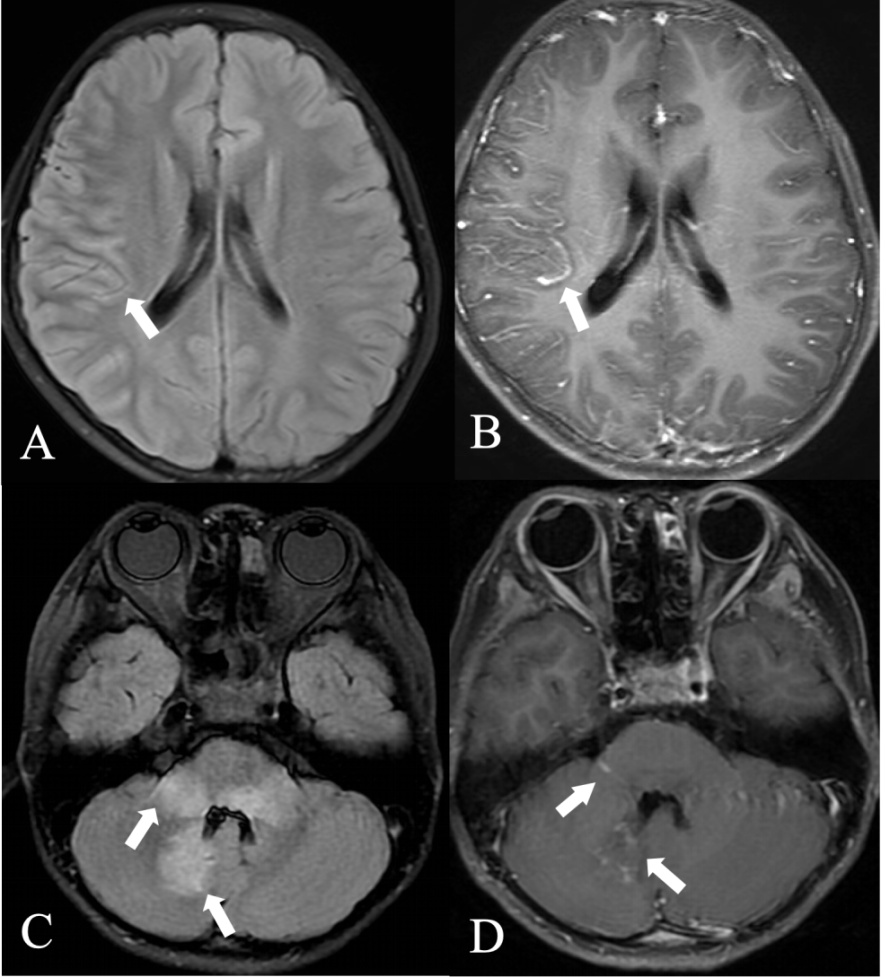

MRI上的视神经强化模式也有助于MOG神经炎的诊断。几乎所有MOG视神经炎发作时都可见到累及广泛的双侧视神经强化特点,其特征性表现为也可累及周围的眼眶组织,视神经鞘或球周脂肪强化,称为神经周围增强[13] (图1)。这是MOG视神经炎最典型的特征,这有助于区分AQP4-IgG血清阳性或MS相关的视神经炎[14] [15]。广泛的视神经周围强化也高度提示抗MOG抗体相关的视神经炎[16]

在T2加权像上显示右侧视神经前段信号稍高,边缘稍模糊(A,轴位,箭头;B,冠状位,箭头),T1增强图像上相应的视神经和鞘强化(C,轴位,箭头;D,冠状位,箭头)。

Figure 1. Orbital MRI plain scan and enhancement in optic neuritis with MOGAD

1. MOGAD视神经炎的眼眶MRI平扫及增强

所以,如果患者在发病时出现视盘水肿或在MRI上发现视神经肿胀和视神经增厚或迂曲与神经周围强化,则应高度怀疑MOG-IgG阳性[14]。这种基于MRI发现的早期特点可能具有重要的治疗意义。